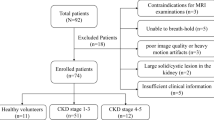

In our retrospective study, we identified 107 patients diagnosed with CKD who underwent noncontrast-enhanced SSFP MRI with spatially selective IR pulse at Tachikawa General Hospital between February 2015 and July 2016. Clinical evaluations were conducted within a week after MRI examination. Patients were excluded from the study if they had a single kidney, a large solid/cystic lesion in the kidney, autosomal dominant polycystic kidney disease, acute kidney injury, unacceptable image quality, or insufficient medical information. Patients with a rotated kidney were also excluded because of the possible incorrectness of measuring morphological parameters. The Institutional Review Board of Tachikawa General Hospital approved this retrospective study (approval number 12000056) and the patients provided written informed consent.

A total of 107 patients diagnosed with CKD were enrolled in this study. Table 1 presents the background profiles of the entire study population. The median age was 64 years and 60.7% of the patients were men. The mean eGFR, raw eGFR, and 24-h creatinine clearance (Ccr) were 51.1 ± 22.7 mL/min/1.73 m2 (range 8.4–130.2), 53.7 ± 25.4 mL/min (range 7.6–118.6), and 67.6 ± 31.7 mL/min (range 4.0–179.0), respectively. The numbers and percentages of patients with each CKD stage were as follows: CKD G1, four (3.7%); G2, 35 (32.7%); G3, 48 (44.9%); G4, 13 (12.1%); G5, seven (6.5%). Anti-hypertensive agents were used in 93 (86.9%) patients, and 73 patients (68.2%) were treated with renin–angiotensin system (RAS) inhibitors, whereas 14 patients (13.1%) were treated with diuretics. Renal corticomedullary differentiation was clearly depicted in SSFP images using standard TI, but not in conventional IP images at even 3.0-T unit MRI (Fig. 1). The mean corticomedullary contrast ratio was higher in SSFP images than in IP images with some exceptional cases (Fig. 2), and the corticomedullary contrast ratio in SSFP images positively correlated with all of the three kidney functional parameters (Fig. 3). Then three morphological variables, minimal cortical thickness, cortical area, and medullary area of all patients were subjected to the validation study of interobserver reproducibility, and each ICC demonstrated a good correlation (Table 2). Average values of the measured kidney morphological parameters are shown in Table 3.